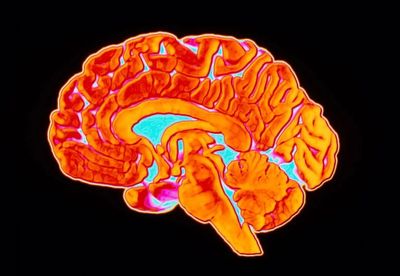

Очищение мозга от токсичных белков недостаточно для победы над болезнью Альцгеймера

Ученые пришли к выводу, что удаление белков амилоида из ткани головного мозга хоть и приводит к некоторым положительным изменениям, но такая стратегия не может восстановить утраченные функции. Результаты исследования вновь демонстрируют, что природа нейродегенерации намного сложнее, чем принято считать.

Ученые обнаружили, что воздействие на спящие гены обращает вспять снижение когнитивных функций. Открытие предлагает новые возможности для профилактики и лечения деменции, а также указывает на необходимость целостного подхода в изучении природы нейродегенерации.